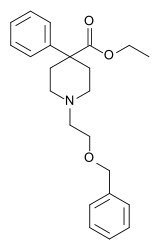

The first fully synthetic opioid was meperidine (later demerol), found serendipitously by German chemist Otto Eisleb (or Eislib) at IG Farben in 1932.[228] Meperidine was the first opiate to have a structure unrelated to morphine, but with opiate-like properties.[199] Its analgesic effects were discovered by Otto Schaumann in 1939.[228] Gustav Ehrhart and Max Bockmühl, also at IG Farben, built on the work of Eisleb and Schaumann. They developed "Hoechst 10820" (later methadone) around 1937.[230] In 1959 the Belgian physician Paul Janssen developed fentanyl, a synthetic drug with 30 to 50 times the potency of heroin.[211][231] Nearly 150 synthetic opioids are now known.[228]